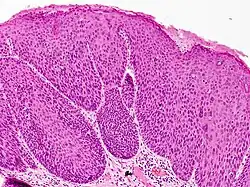

Pathologie

In der lichtmikroskopischen Untersuchung sieht man eine umschriebene Verbreiterung der Epidermis (Oberhaut) mit Hyper- und/oder Parakeratose (überschießende bzw. gestörte Verhornung). Die Schichtung der Epidermis ist aufgehoben und die Zellkerne der Keratinozyten (hornbildende Zellen der Oberhaut) variieren in Form, Größe und Chromatindichte. Als Zeichen der unkontrollierten Zellteilung findet man Mitosen (Kernteilungsfiguren) in der gesamten Epithelbreite sowie Dyskeratosen (vorzeitig verhornte Keratinozyten). Besonders in den oberflächlichen Anteilen der Epidermis kann sich eine HPV-typische Koilozytose (zytoplasmatische Hofbildung um den Zellkern) zeigen.[11][7]

In der immunhistochemischen Färbung auf p16 färben sich Zellkerne und Zytoplasma der Keratinozyten in der gesamten Breite der Epidermis kräftig an.[12]